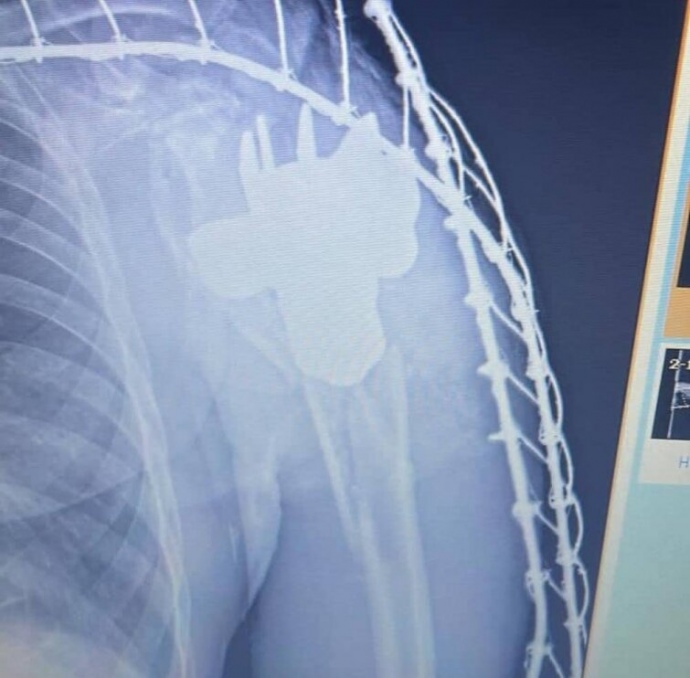

Military medics at a frontline hospital removed a mine shank from the body of a wounded soldier.

The photos of the recovered piece of explosive were shared by the Medical Forces Command of the Armed Forces of Ukraine.

During further examination, doctors found a foreign piece in the wounded man's body, the contours of which resembled a mine shank.